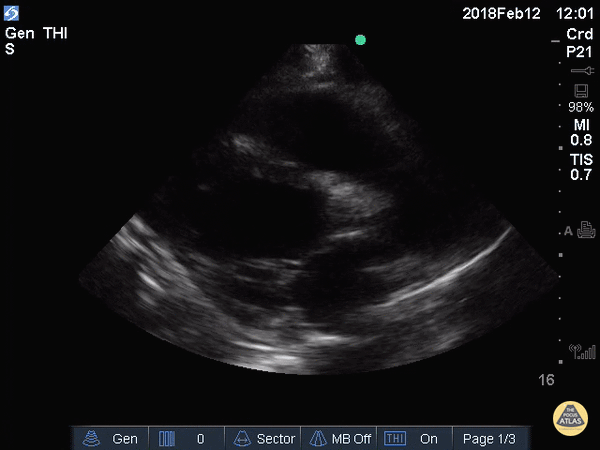

Left Ventricular Dysfunction - Decreased EF (Parasternal Long)

An elderly gentleman w/ non-ischemic cardiomyopathy 2/2 meth use and a very poor EF. EPSS was 2.21 when measured in parasternal long axis correlating with severely reduce ejection fraction. Greg Powell, MD